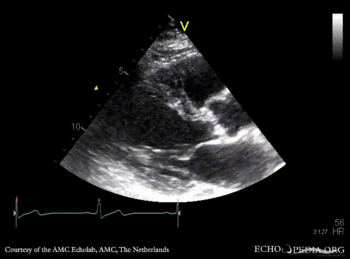

PLAX: stenotic aortic valve, left ventricle hypertrophy PLAX with Color Doppler: mild aortic regurgitation